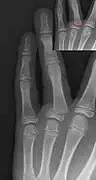

Salter–Harris III fracture of big toe proximal phalanx. -